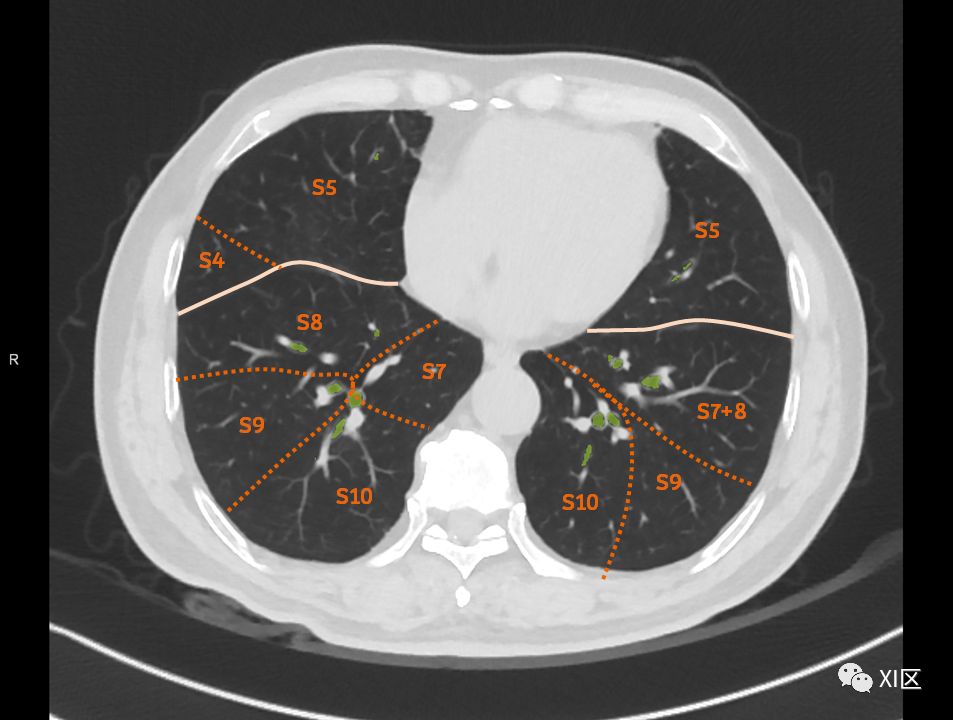

在进行肺的分段时,可以上下观察浏览,沿着相应气管的走形可以更容易准确地进行分段。

肺的断层分段示意图